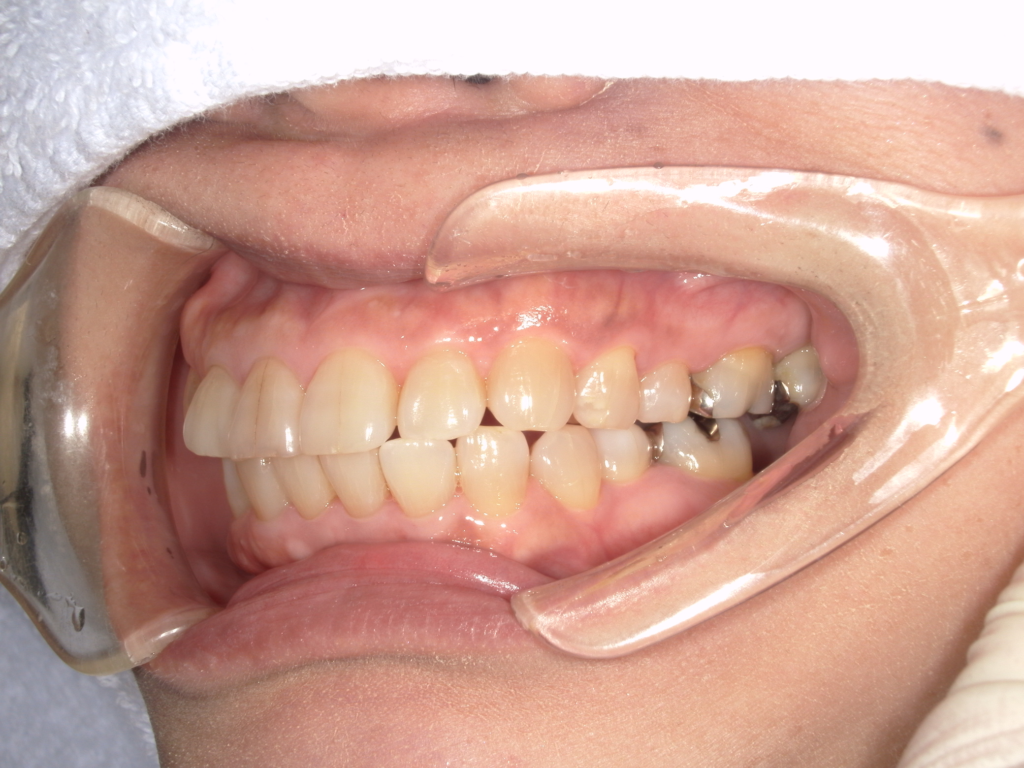

Y様インプラント実例 #44

左の上下の奥歯をインプラントで治療しています。

左下の奥歯は歯を抜くのと同時にインプラントの埋め込みを行っています。

被せものは上下、セラミックスで作っています。

治療前

治療後